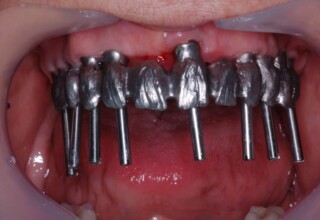

Ολική Στοματική Αποκατάσταση σε Εμφυτεύματα με διαφορετική προσέγγιση στην Άνω και Κάτω Γνάθο

Κάτω γνάθος: εξαγωγές, άμεση τοποθέτηση εμφυτευμάτων και άμεση φόρτιση(την ίδια ημέρα) με προσωρινή γέφυρα

Άνω γνάθος: σταδιακές εξαγωγές, σταδιακή τοποθέτηση εμφυτευμάτων και σταδιακή ενσωμάτωση τους στην προσωρινή γέφυρα ώστε η ασθενής να μην μείνει ούτε μια ημέρα χωρίς αποκατάσταση. Στόχος η συνεχής λειτουργική και αισθητική αποκατάσταση της ασθενούς χωρίς άμεση φόρτιση των εμφυτευμάτων λόγω ανατομικών ιδιαιτεροτήτων.

Χρησιμοποιήθηκαν παλαιές χαμογελαστές φωτογραφίες της ασθενούς γιατί είχε χαθεί τελείως το φυσικό σχήμα των δοντιών εξαιτίας των πολλαπλών προσθετικών προσπαθειών που είχαν γίνει στο παρελθόν. Μεταφέρθηκε στην προσωρινή γέφυρα η σχέση των φυσικών δοντιών μεταξύ τους άλλα και με τα χείλη. Δοκιμάστηκε η φώνηση και η μάσηση με δυο διαφορετικές προσωρινές άνω γέφυρες και εκτιμήθηκε η αισθητική απόδοση τους. Αφού επιτεύχθηκαν σε βαθμό ικανοποιητικό η φώνηση και η αισθητική εμφάνιση της οδοντοφυΐας, η προσωρινή αποκατάσταση χρησιμοποιήθηκε ως οδηγός για την τελική.

Αρχικό

Ενδιάμεσο

Τελικό